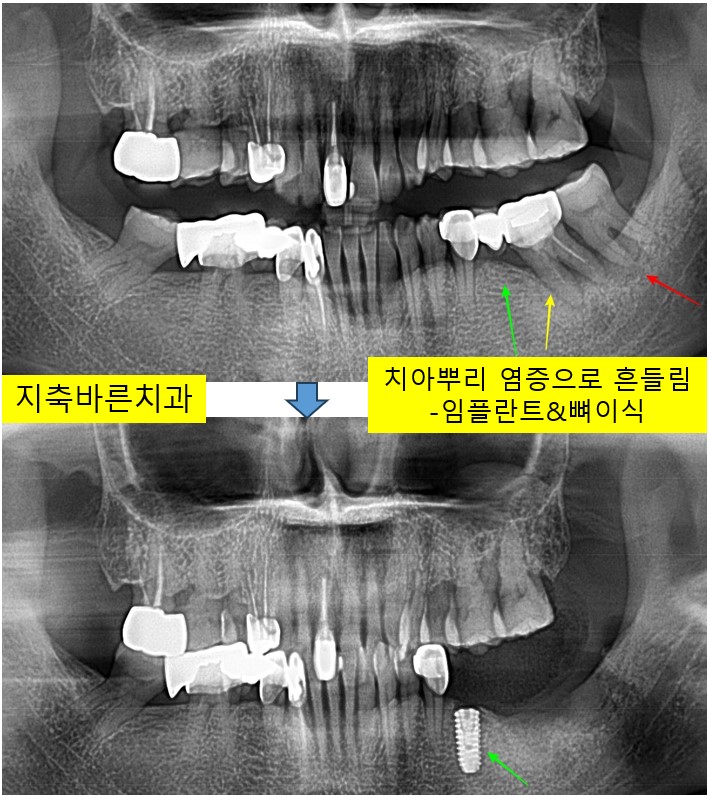

<치아 염증으로 브릿지 커팅 후 임플란트&뼈이식>지축치과 지축역치과 삼송치과 원흥치과 원당치과 화정치과 구파발치과 불광치과 양주치과 탄현치과 도래울치과 마두치과 파주치과 주엽치과2

왼쪽 아래 치아가 시리고, 흔들리며 불편하다고 2024년 7월 60대 Rㅁㅁ 님께서 내원해주셨습니다. 1. 처음...